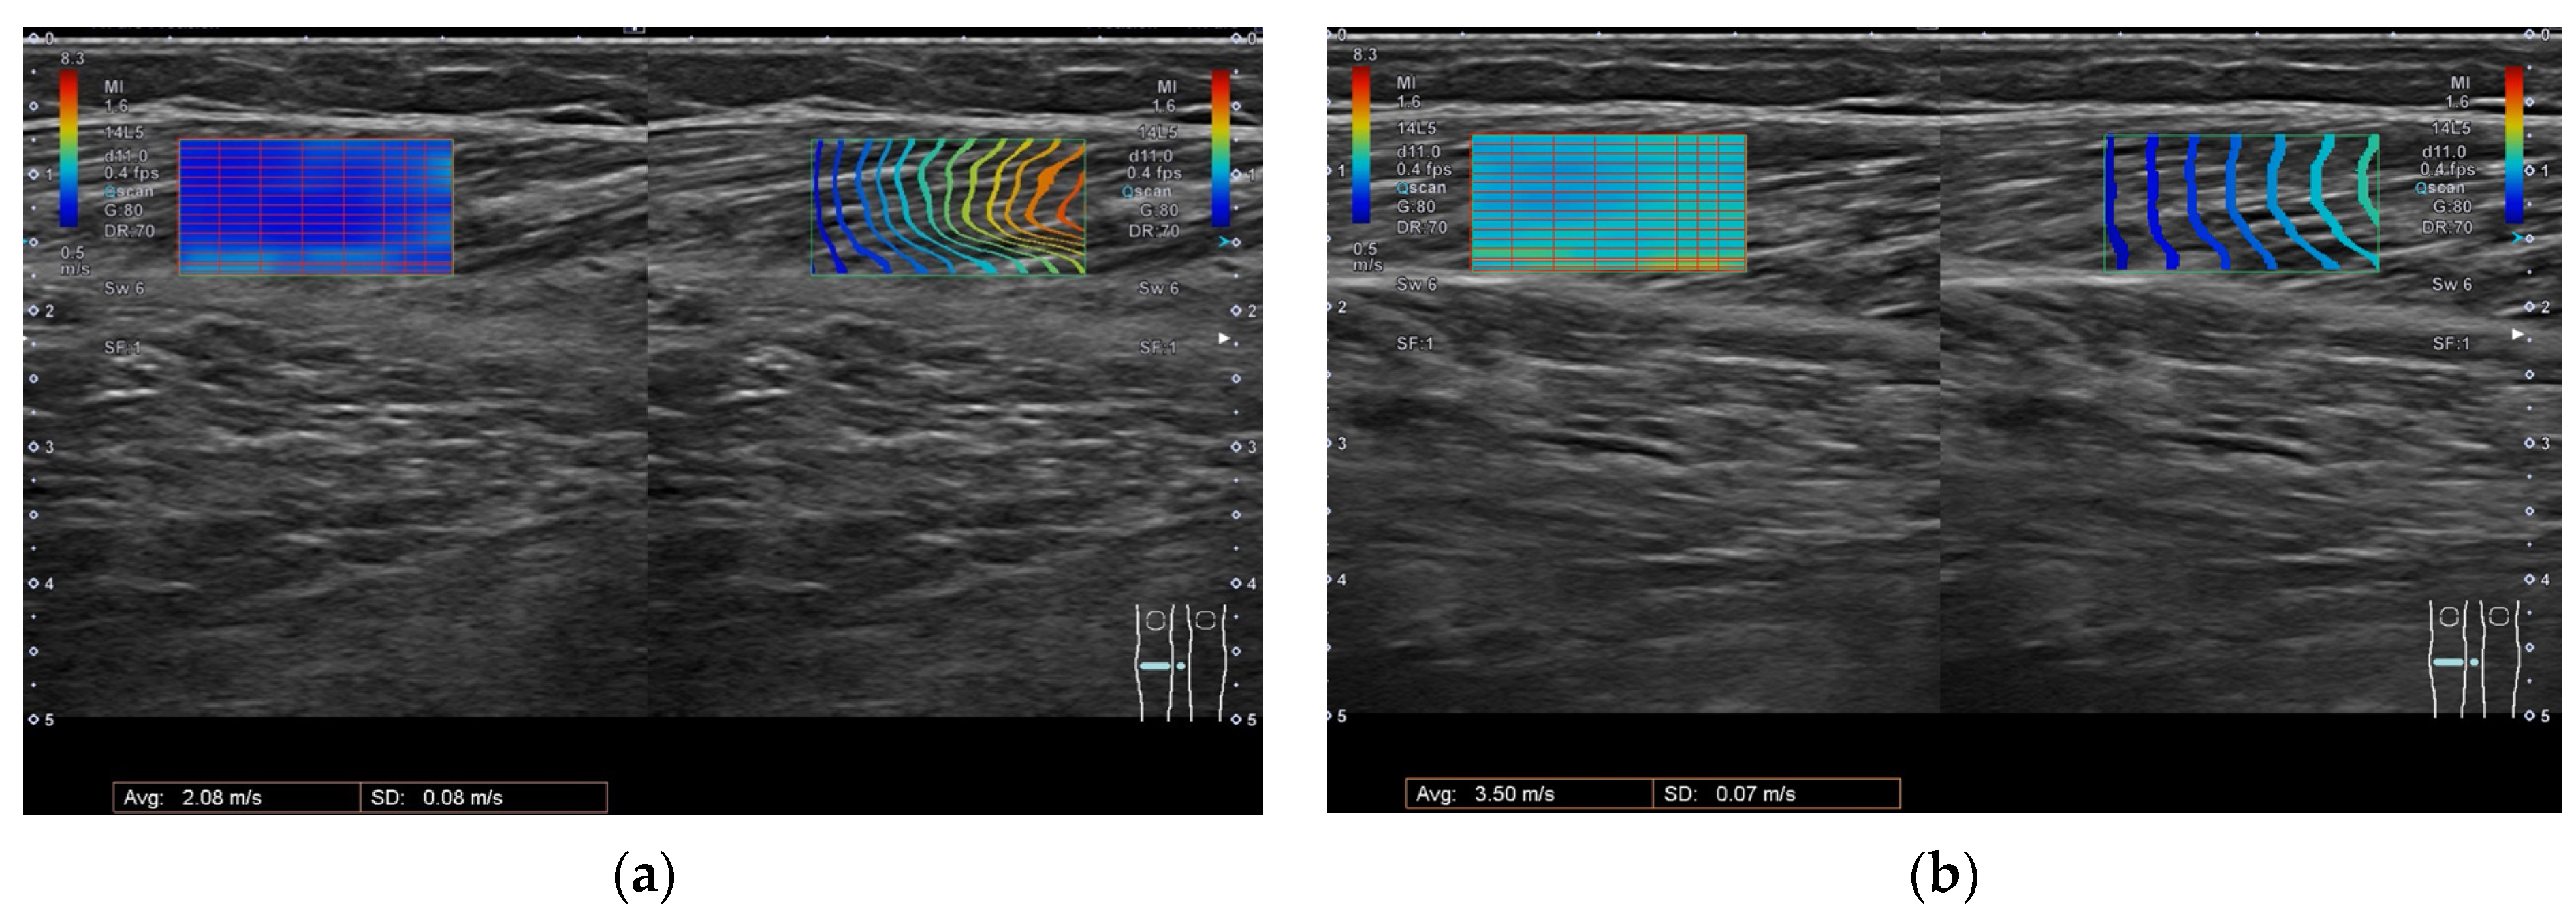

2.2. Changes after BoNT-A Injection and Correlations between SWV and Clinical Examinations

5.2. Ultrasonography

| SWV at rest (m/s) (Median (IQR)) | 2.52 (2.21–2.67) | 2.24 (2.00–2.42) | 0.093 |

| SWV stretched (m/s) (Median (IQR)) | 4.00 (3.47–6.77) | 2.98 (2.74–3.52) | * 0.005 |